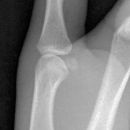

Bennett Fraktur mit geringer Dislokation

Es wurden keine Bilder gefunden.